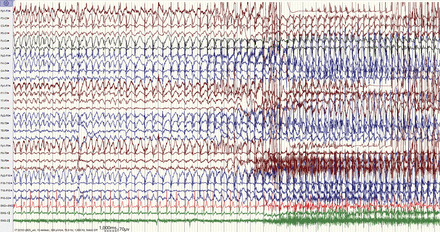

图1和图2癫痫的脑电图记录显示示例。Video-EEG文件可以在森林女神(见方法)的数据可用性部分。

绿色的2通道表面三角肌肌电图记录从左和右(EMG 1/2)。广义棘波爆发持续而强直性肌肉活动建立。ABTC = absence-to-bilateral-tonic-clonic。

6频道在绿色表面EMG记录从左和右三角肌(EMG 1/2),肱二头肌(EMG 3/4),以及前胫骨(EMG 5/6)的肌肉。广义棘波爆发逐渐取代进化猝发的节奏(低烈度快速活动)。ABTC = absence-to-bilateral-tonic-clonic。

全部12个发作开始的最初阶段受损的意识。在3例,这是长时间(在病人3和6分钟> 30分钟的病人4和5);在剩下的病人,其持续时间是5 - 28秒(值10秒,四分位范围7 - 15秒)。在所有患者中,两国同步(广义)痫性放电脉冲记录初始时期的不良意识:广义棘波放电4例和混合飙升和polyspike和慢波放电8例。在6例,不规则破裂,6例,他们有节奏的(2.5 4赫兹)。这个初始阶段的癫痫发作的electroclinical特性是广义的类似nonmotor(缺席)癫痫持续状态发作与否(在延长患者初始阶段)。在所有患者中,广义tonic-clonic行为直接跟着意识受损的初始阶段,没有回到基线认知能力在剧烈运动前发生。患者5例(6 - 9和11),迫使版本是观察到主音的开始阶段。患者7例(1 - 7),广义/ polyspike飙升和慢波爆发直到脑电图成为被肌肉构件(图1)。患者5例(8 - 12),高频(βα)猝发的节奏与进化时间出现在主音的开始阶段(图2)。